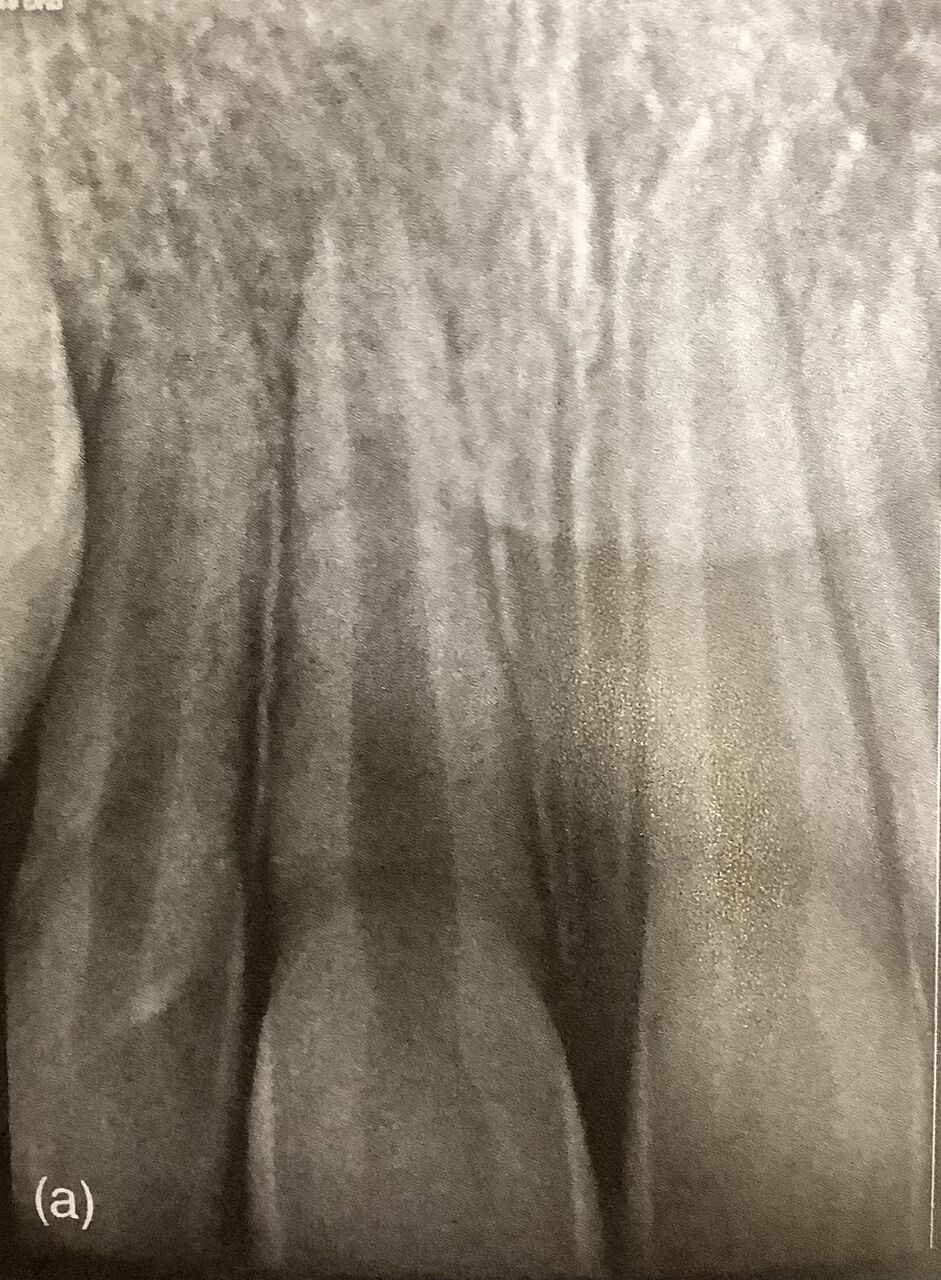

最近は出来るだけ小さく削るのが注目されています。

出来るだけ多くの象牙質を残すためです。

神経の部屋の天井部分を多く残すことで、折れにくくなります。